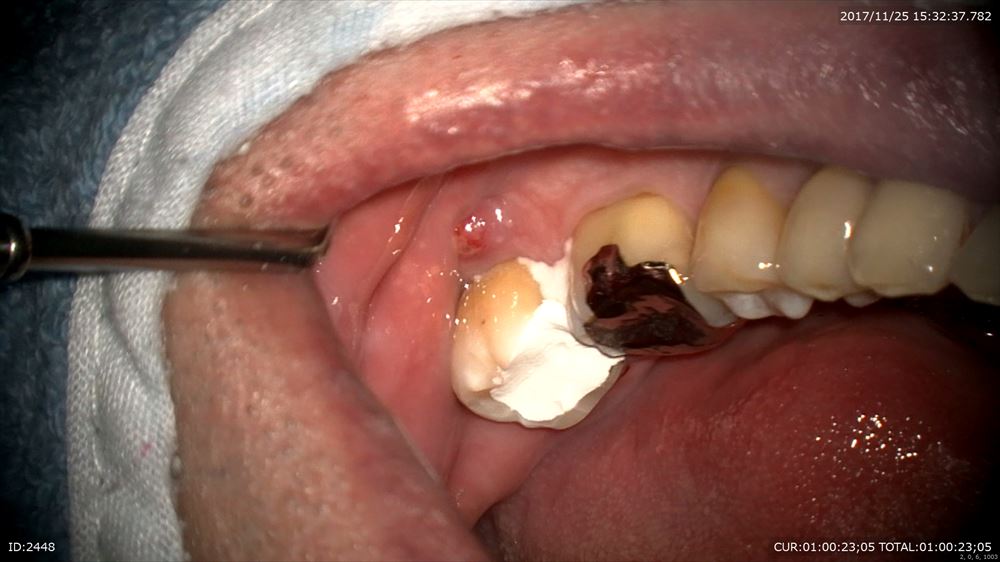

以前から腫れが引かないと悩まれていた方。とても心配していました。

左下が腫れていました。

根管を清潔にする事が出来て

結果が出てきました。

術前左、術後右

次回根管充填です。